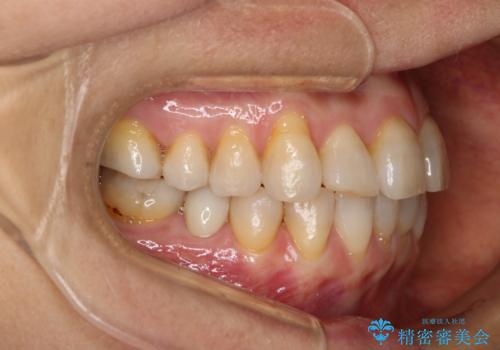

前歯の反対咬合、奥に引っ込んでしまっている歯をインビザラインで治療する

- インビザラインでの治療を希望した患者様です。

上の前歯の反対咬合があり、治療の途中で下の前歯を乗り越える必要があります。

前歯を乗り越える治療はワイヤーの方が有利ではありますが、インビザライン単独でも行うことができます。

患者様によっては乗り越えるタイミングだけワイヤーを装着し、そのあとでまたインビザラインに戻るという方もいらっしゃいます。

咬みにくい時期を最小限にしたい方はお勧めです。